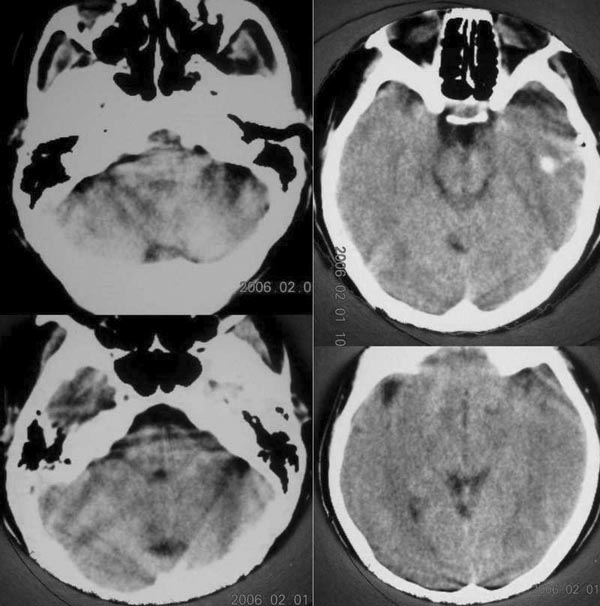

标题: CT2672:[原创]女30岁,头痛右枕部稍高密度影. [打印本页]

标题: CT2672:[原创]女30岁,头痛右枕部稍高密度影.

图像不是太好.第三幅图右侧稍高密度影可能是伪影!

象伪影,细看两侧都有,右侧打点。

颅底伪影太明显,应该薄扫